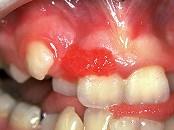

组图是牙龈瘤患者,有关此病的描述不正确的是()A.生长较慢B.肿块较局限C.可能导致牙松动D.为恶性病变E.可破坏牙槽骨壁

问题 组图是牙龈瘤患者,有关此病的描述不正确的是()

选项 A.生长较慢 B.肿块较局限 C.可能导致牙松动 D.为恶性病变 E.可破坏牙槽骨壁

答案 D